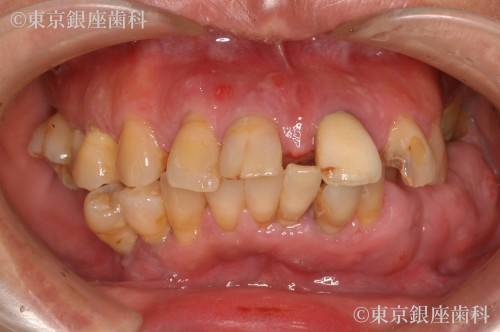

全体的な歯周病、歯が動いて出っ歯になってしまった

Before

50代 女性

疾患 歯周病

施術内容 ワンデイインプラント

治療期間 11か月 費用 670万円(税込)

ワンデイインプラントで審美を回復

上下のワンデイインプラントを実施

鳥貌を改善